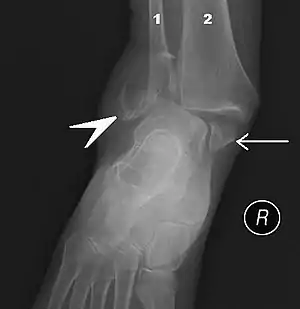

| Fracture of both sides of the ankle with dislocation as seen on anteroposterior X-ray. (1) fibula, (2) tibia, (arrow) medial malleolus, (arrowhead) lateral malleolus | |